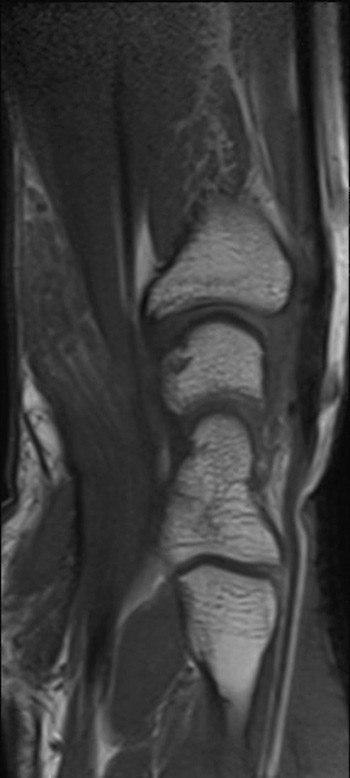

En tidligere frisk jente i tenårene ble henvist til håndkirurgisk avdeling med en kul på bøyesiden ved venstre håndledd. Denne var blitt oppdaget av mor rundt syv år tidligere og var etter hvert blitt økende smertefull. Pasienten beskrev overfølsomhet for berøring og nummenhet i tommel, peke-, lang- og ringfinger. Perkusjon over tumor ga utstrålende smerter og økt nummenhet i de samme fingrene. MR-undersøkelse viste en fortykket medianusnerve med utseende som en kabel på grunn av fibrøs fortykkelse av peri- og endonevrium og økt mengde fett som separerer de ca. 15 nerveaksonene (bilder på nett). Tumorens utbredelse var ca. 10 cm. Tilstanden ble diagnostisert som et lipofibromatøst hamartom på grunn av MR-funnene, som angis som patognomoniske for tilstanden (1).

Det ble gjort eksplorasjon av tumor og dekompresjon av nerven i karpaltunnelen. Bildet viser tumoren, som på det tykkeste hadde 3 × større diameter enn en normal nerve. Ved kontroll to og seks måneder senere hadde pasienten de samme smerteplagene som før operasjonen, men følesansen i fingrene var forbedret. Nevrografi etter to måneder viste moderat aksonal og demyeliniserende sensorimotorisk affeksjon av medianusnerven i håndledds- og håndrotsnivå, tydende på kompresjonsnevropati. EMG-undersøkelse viste sparsom denervasjonsaktivitet og funn som ved gjennomgått reinnervasjon. Det var ingen tidligere undersøkelser som man kunne sammenligne med.